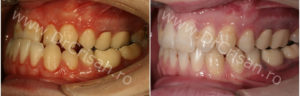

Fotografie laterala dreapta Inainte/Dupa tratament

Fotografie laterala stanga Inainte/Dupa tratament